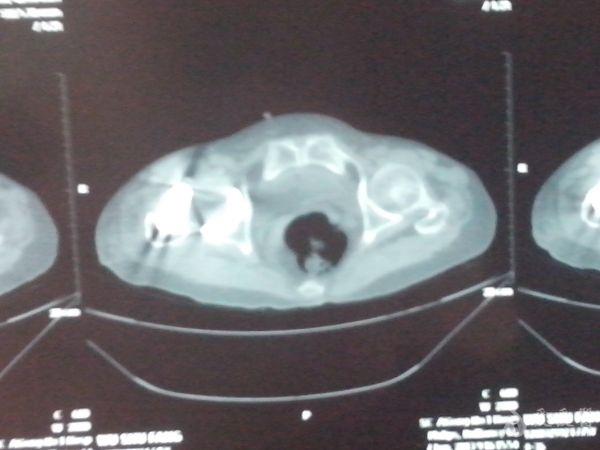

患者为75岁老年女性,因反复右髋部疼痛8+月,不能行走10+天入院。查体主要是右髋关节的压痛、叩痛,关节活动受限,右下肢无明显短缩。入院行X线片检查后发现右股骨颈陈旧性骨折(头下型)。追问病史发现患者在数年前曾有右髋部跌伤史,由于能忍痛行走,所以没有就诊。经科室讨论诊断为“右股骨颈头下型骨折(陈旧性),右股骨头缺血性坏死”。在完善术前检查后予在全麻下行“右人工全髋关节置换术”。术中顺利,时候予头孢呋辛、克林霉素抗感染治疗,低分子肝素钠抗凝治疗,以及对症支持治疗。让人最担心的事情出现了,术后不到24小时,患者右髋关节脱位了,并且出现的是前脱位,遂即在全麻下行手法复位,复位后外展、外旋、屈曲髋关节均无脱位发生,甚至轻度内收内旋都不脱位。以为是患者体味的问题。随之出现的是之后的10天左右时间里,患者右髋关节反复脱位,均是前脱位,并且发现在右下肢位于外展位时发生脱位,稍微牵引右下肢并内收既能复位。患者于今日上午再次发生脱位,脱位发生在右下肢伸直、外旋约5°,在牵引并内旋后可以轻松脱位,再伸直并轻微外旋又能轻松脱位。反复观看患者的X线片,考虑原因1、髋臼杯前倾角过大(粗略测了下大概有24°多);2、股骨柄过短所致。本打算做翻修,但向上级医院的教授请教后(教授并未直接看到患者),建议予髋人字石膏外固定3个月,于是在下午做了石膏固定。目前的问题是:1、石膏外固定三个月有效果吗?2、三个月去除石膏后在发生脱位怎么办?3、**已经不可避免,请各位老师看看我们主要的问题在哪里?是不是我们所考虑的前倾角和股骨柄的问题?4、手术指征是否存在问题?手术是我们一位德高望重的老师做的,大家都觉得很遗憾,最近我们科所有的医生都被这个事情给弄得郁闷了,气氛好压抑。

3、复位后复查的片子,这个也是唯一一张关节在位时拍的片子,之后患者就出现反复脱位。

4、最后一次脱位的片子。